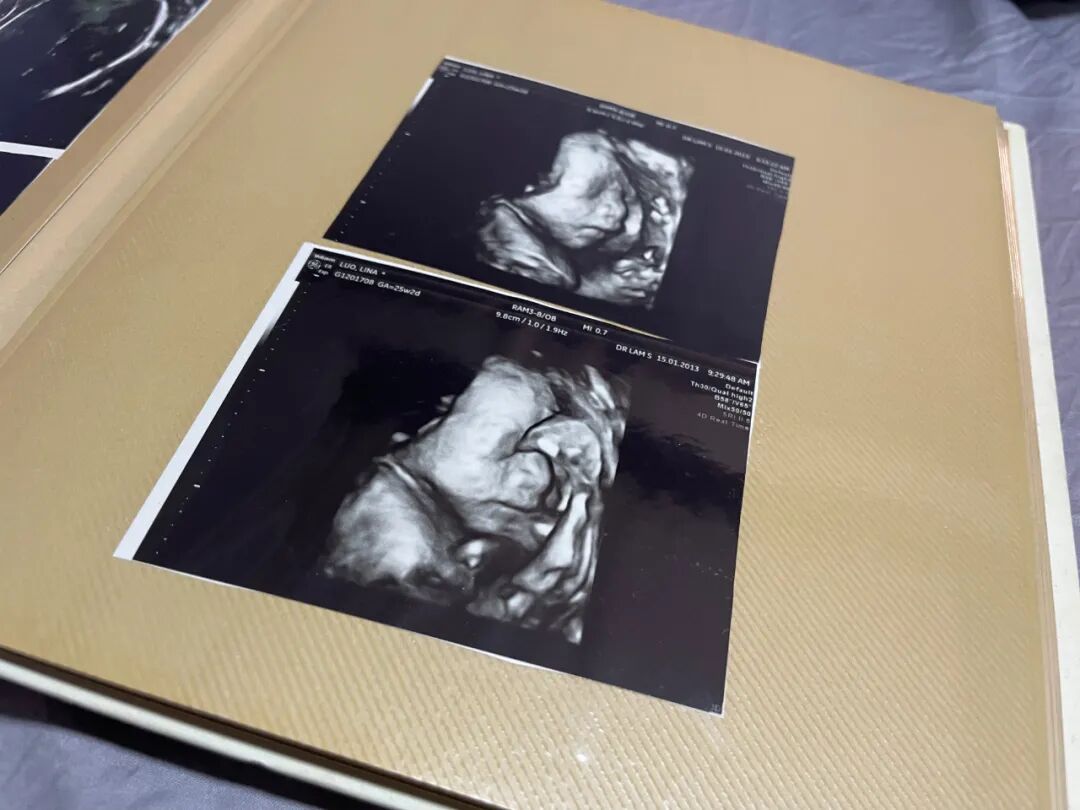

可以结合孕期的照片跟孩子说,当孩子在妈妈肚子里长大时,妈妈的肚子也会变大,这是因为你在子宫里长大。▼

这是我的B超照片,我一直留着,虽然孩子看着胎儿的自己也会懵,他们最诧异的其实是为什么在我肚子里可以几十厘米,出生后他可以长到一米多……